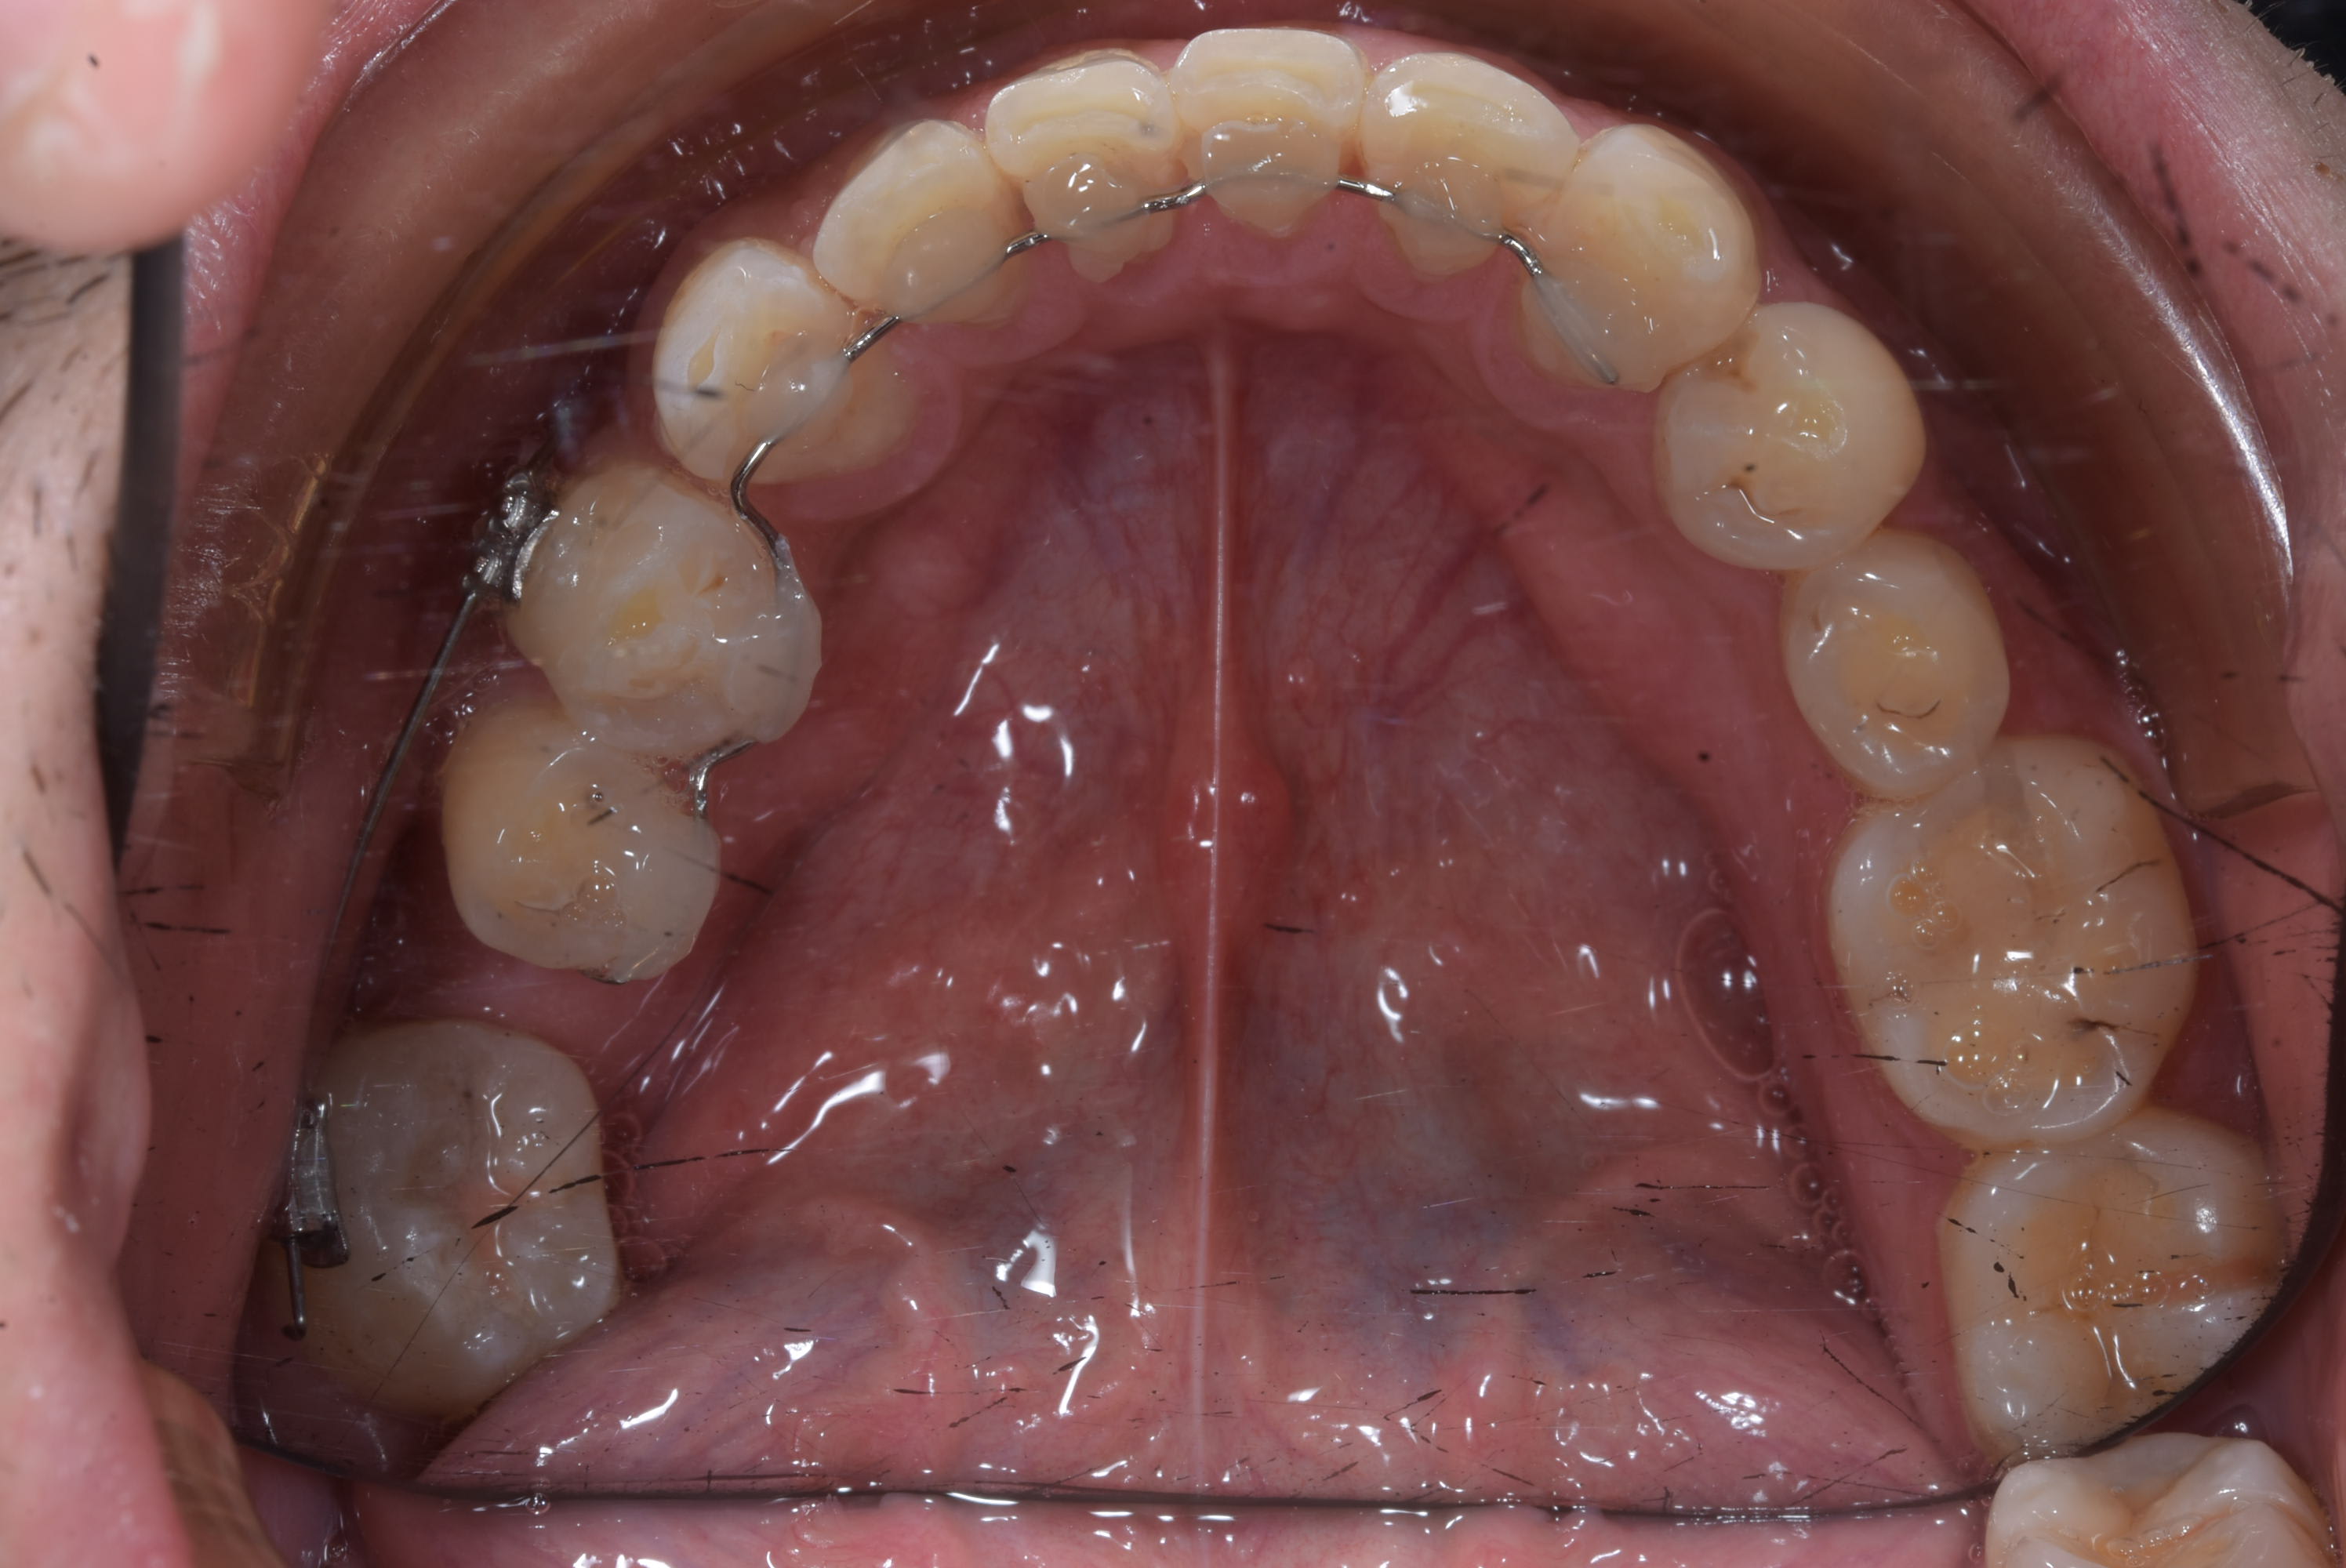

La solution :

- Prendre une empreinte alignate ( ou utiliser les modéles d'étude )

- Plier un file SS 0.02 en lingual de 45 à 33

- le fixer comme une barre de contention

- mettre un bracket sur 44 et 47

- commencer à aligner la 47 avec un file Niti.

Le file est SS 0.02 et vue que je plie mois même mes contention fixe ( en niti maintenant ) le pliage m'a prie 4 minute. J'ai collé sur le modéle en plâtre 2 minutes puis en bouche :-) . Poser les bracket m'a prit plus de temps.